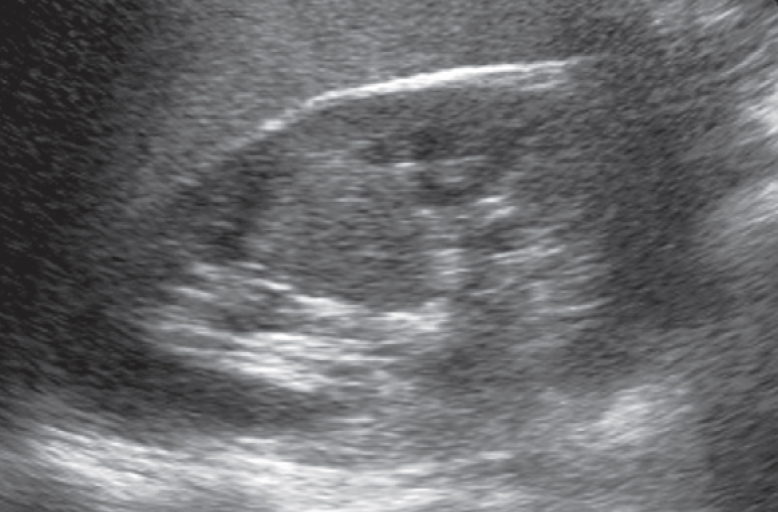

3-Duplex kidney

هذا مصطلح واسع يشمل عدة متغيرات منها وجود كليتين ملتصقات ببعض أو وجود two collecting systems في كلية واحدة. وهذه أيضا يوجد بها متغيرات أخرى من ناحية وجود حالب واحد أو حالبين ووجود شريان واحد أو اثنين.

يوجد هذا المتغير في قرابة ١٠٪ من الناس الطبيعيين. ويجب على الأخصائي التأكد من عدم توسع الحالبين وأيضا عدم وجود انسداد في أحد collecting systems وتحديدا العلوي.